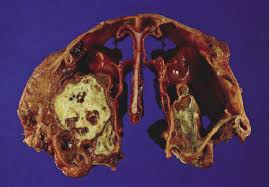

The Case Of The Stertorous Kitty

The Case Of The Stertorous Kitty from www.veterinarypracticenews.com